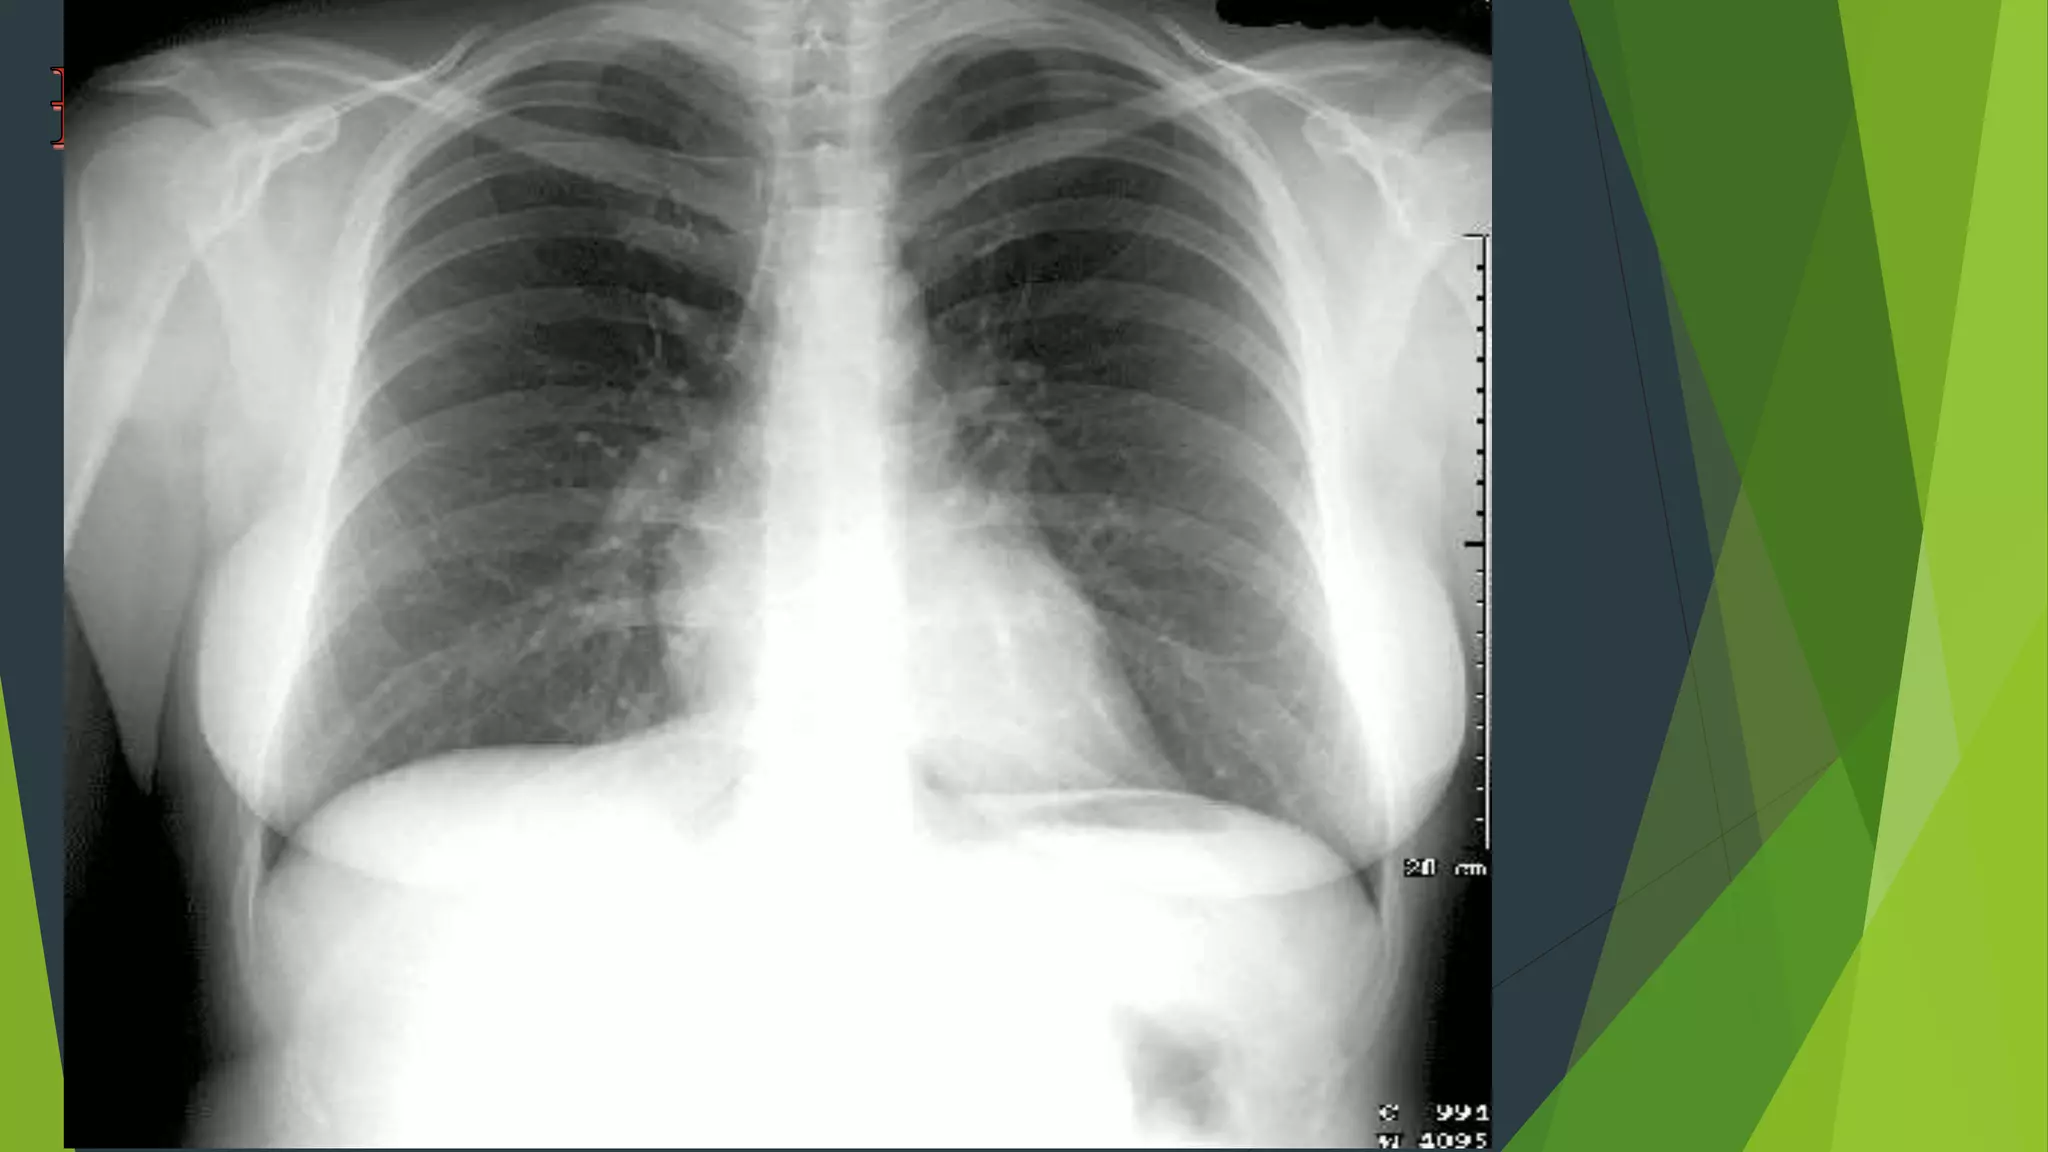

1. Hoàn toàn thẳng: bờ trong xương đòn đối xứng nhau qua

đường giữa Cân xứng : mức hơi dịch ở túi hơi dạ dày, hai

xương bả vai tách ra khỏi lồng ngực.

2. Hít vào đủ sâu: cung trước xương sườn 6 - 7 trên vòm

hoành. Cung sau ở xương sườn 10 trở xuống

3. Độ đối quang tốt : Thấy được 3 - 4 đốt sống ngực

trên,thấy được mạch máu sau tim gan, thấy mạch máu

cách ngoại vi phổi 1-2cm.

Độ thẳng cân xứng

Hít đủ sâu ?